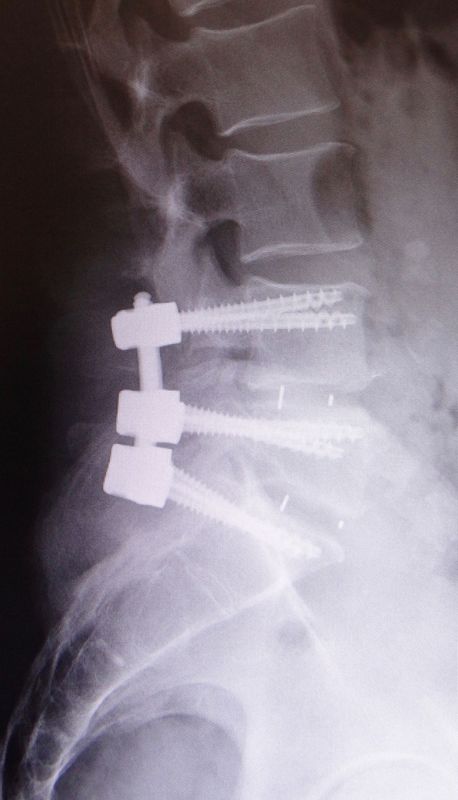

Un traitement est nécessaire lorsque le spondylolisthésis entraîne des douleurs importantes ou une baisse de la qualité de vie. Les traitements non chirurgicaux comprennent une modification des activités afin de diminuer les charges/forces sur la colonne vertébrale, la physiothérapie, des médicaments ou des injections pour diminuer la douleur. Quand le traitement conservateur ne fonctionne pas, et que les douleurs ne sont plus supportables, une chirurgie de stabilisation par fixation et fusion (spondylodèse) est proposée.

Des vis sont implantées dans deux ou plusieurs vertèbres afin de fixer l’instabilité. Une ou plusieurs cages sont également placées entre les vertèbres, une fois le disque intervertébral retiré pour permettre une fusion.

Le traitement consiste, dans la plupart des cas, en une chirurgie de décompression de la moelle épinière par discectomie cervicale antérieure et mise en place d’une cage avec plus ou moins une plaque/vis stabilisatrice. Malheureusement, il n’existe pas de traitement conservateur, excepté le soulagement des douleurs. Il est important d’opérer rapidement au moment du diagnostic afin d’éviter une aggravation de la faiblesse des 4 membres.